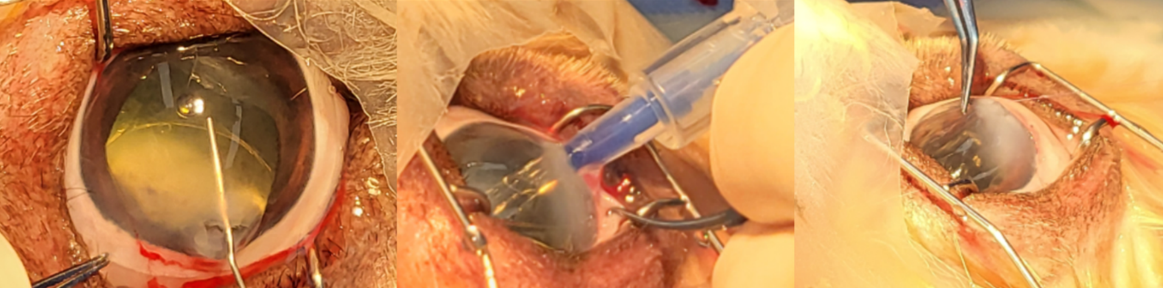

.png)

사진3. 수정체 파열까지 진행된 환자에서 수술적인 교정. 수정체 파열이 심한 경우에 수정체 물질에 의한 추가적인 염증 반응 및 감염으로 인한 지연 감염 증후근(SIS)이 발생할 수 있으므로 수술적인 교정이 필요함.